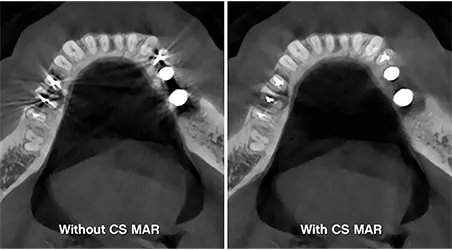

Safer, Low-Dose Technology

Our 3D system uses up to 70% less radiation than conventional X-rays, providing peace of mind without compromising image quality.

• Minimize radiation exposure while improving image clarity